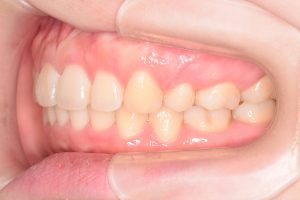

初診時(2022年9月)と装置撤去時(2025年9月)の写真です。

正面

右側

0000000009

0000000137

左側

0000000010

0000000138

・過蓋咬合

・叢生

・左右第二大臼歯シザーズバイト